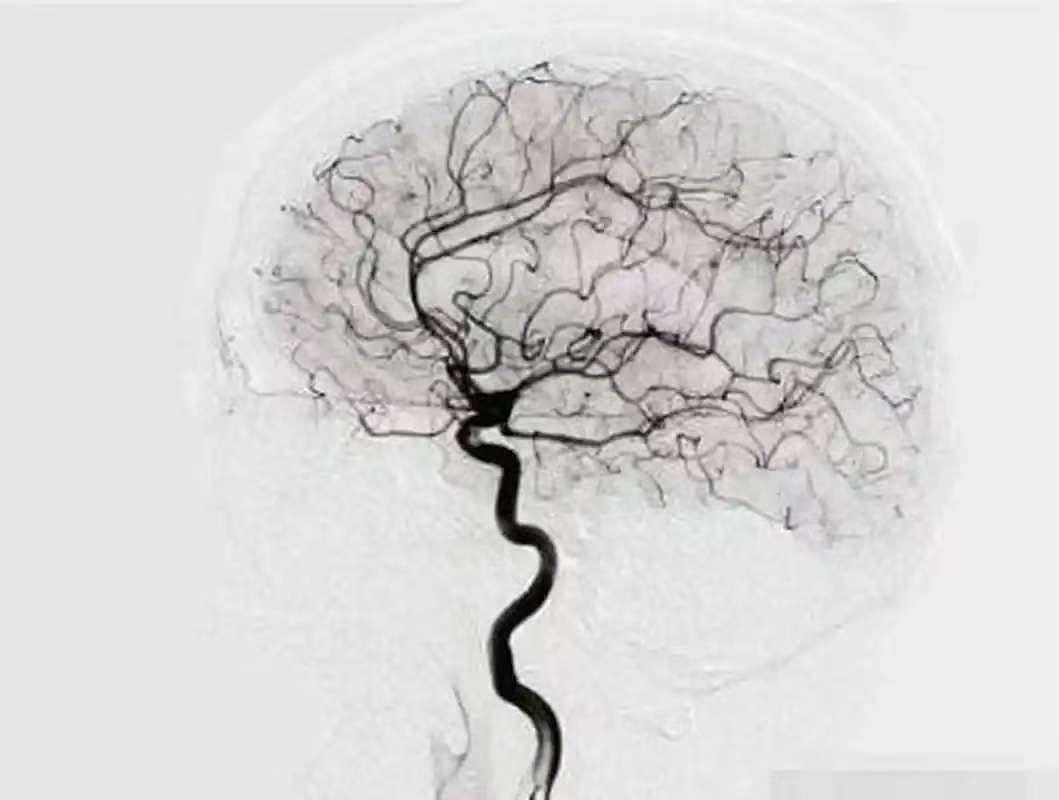

脑血管造影(DSA)检查

脑血管造影(DSA)检查是检查脑血管疾病最有效的方法之一,成为诊断脑血管疾病的“金标准”。它可以通过将软管插入血管,然后注入造影剂来获得血管的详细图像。DSA检查能为动脉瘤、血管狭窄、血管畸形等复杂血管病变的诊断提供非常精确的血管图像。DSA因其高分辨率,能清楚地显示血管的微小结构,帮助医生做出准确的诊断和治疗计划。